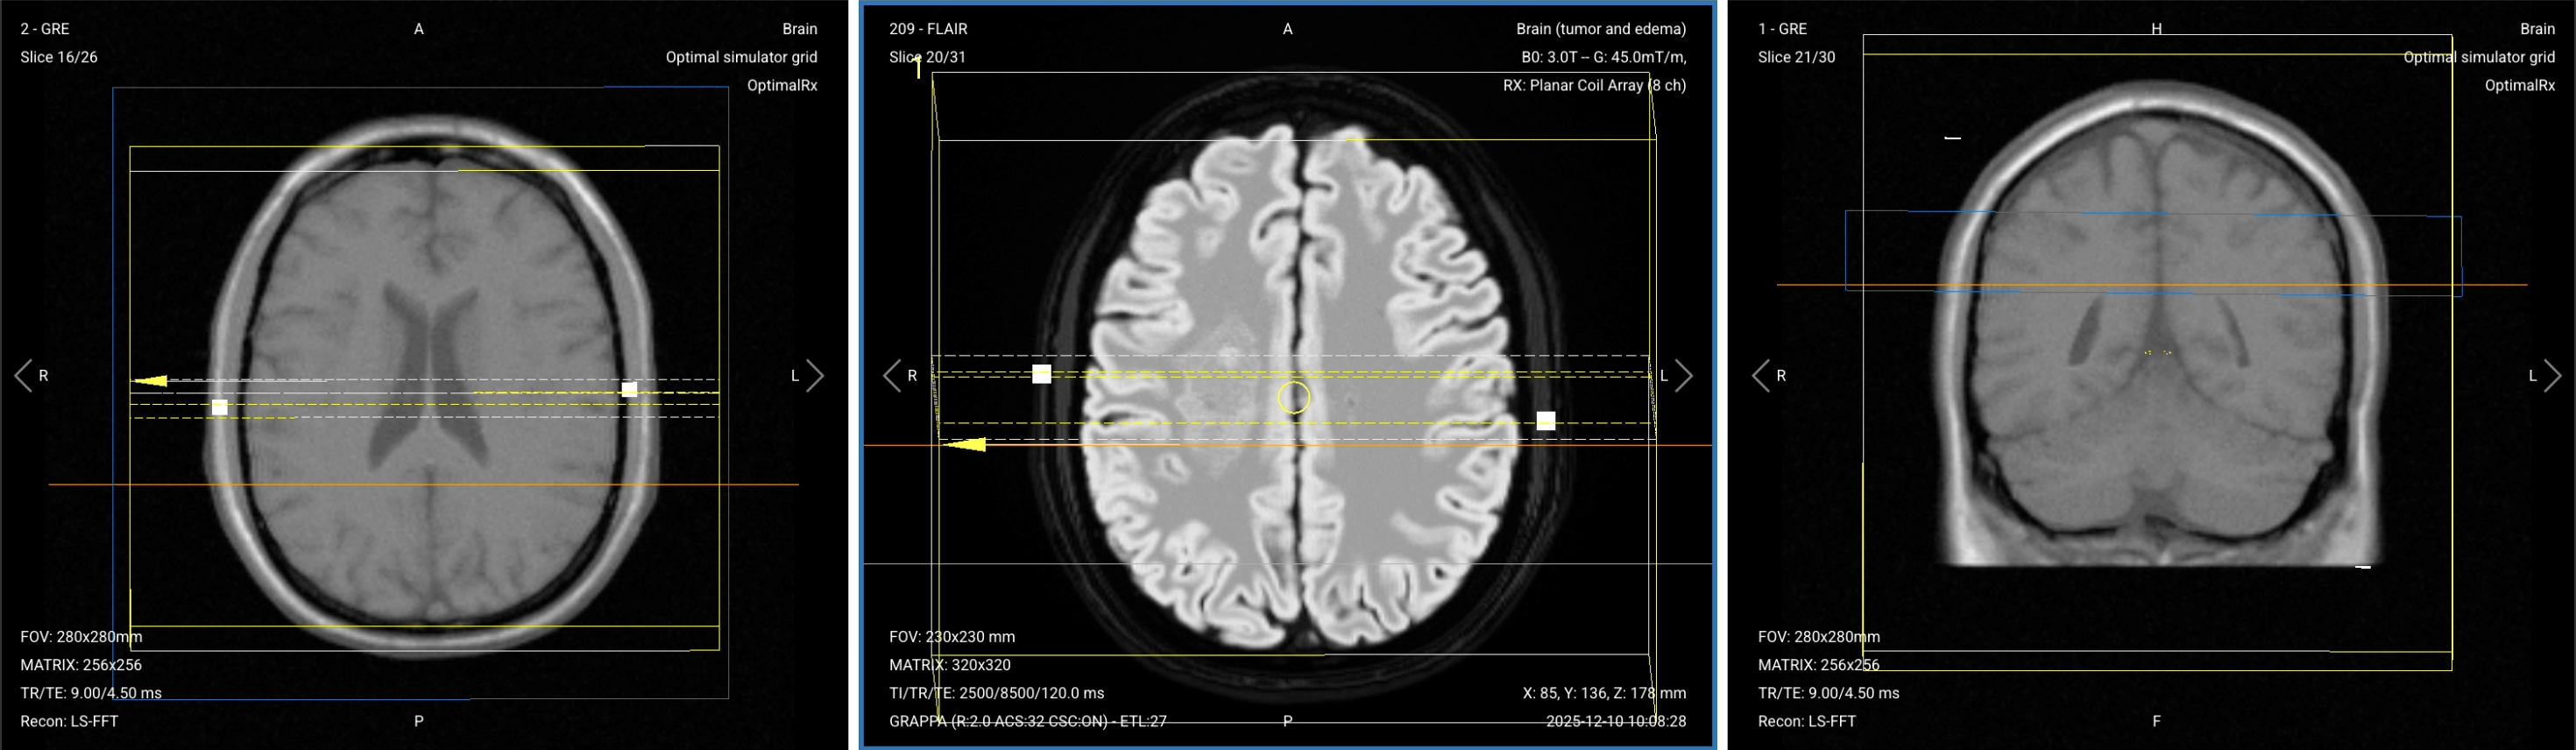

The Contrast Injection Workflow

Understanding the complete workflow helps you plan efficiently and avoid delays after contrast injection. The key principle is: plan all post-contrast sequences before injecting contrast.

For Manual Injection:

1. Insert cannula in patient's arm

2. Position patient at isocenter

3. Acquire all pre-contrast sequences

4. Plan all post-contrast sequences

5. Slide patient table out of bore

6. Enter scan room with prepared syringe

7. Inject contrast slowly through cannula

8. Press isocenter button to reposition patient

9. Return to control room and start post-contrast acquisitions (about 3-5 min after starting the injection)

For Automated Power Injection:

2. Connect IV line from injector to cannula

3. Position patient at isocenter

4. Acquire all pre-contrast sequences

5. Plan all post-contrast sequences

6. Set injection parameters (volume, flow rate, etc.)

7. Initiate injection from control room

8. Wait 3-5 minutes after starting injection, then start post-contrast sequences

In both workflows, Step 4 (planning post-contrast sequences) happens before contrast injection. This ensures zero wasted time after injection.

Part 1: Plan and Set Up the Post-Contrast Sequences

Before we inject contrast, we must plan all post-contrast sequences and have them ready to run. This ensures we don’t waste any time after injection.

The 3 post-contrast sequences of a standard brain tumor MRIs:

1. Sagittal T1 3D MP-RAGE

2. Axial T1 TSE with Fat Suppression

3. Coronal T1 TSE with Fat Suppression

We use T1-weighted sequences after contrast because they show enhancement patterns that guide diagnosis.

3D MP-RAGE is the gold standard for tumor enhancement and abnormal blood-brain barrier breakdown. The fat-suppressed T1 TSE sequences confirm enhancement patterns and eliminate fat signal that could obscure pathology.

In the sections below, we go through how to plan and set up each sequence.